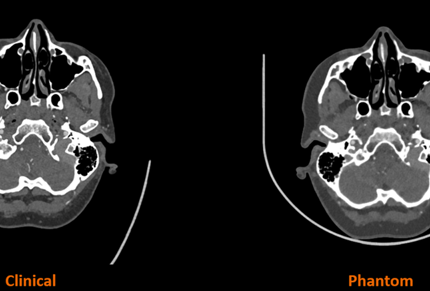

Medical research

3D Printing: A New Dimension for Medical Simulation

Neurosurgical trainees at the All India Institute of Medical Sciences, Delhi (AIIMS Delhi) use Stratasys FDM and PolyJet solutions